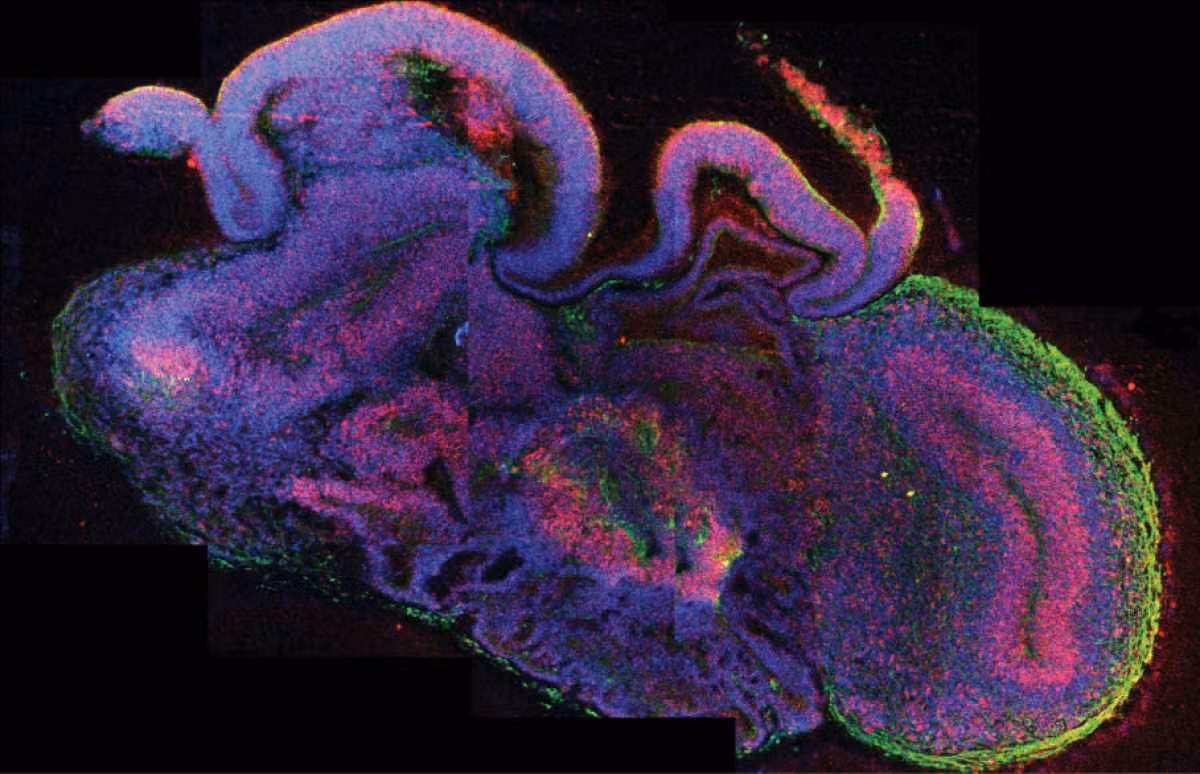

Năm 2013, các nhà khoa học của Viện Công nghệ sinh học phân tử tại Vienna, Áo thông báo họ đã thành công tạo ra một bộ não nhỏ trong phòng thí nghiệm. Bằng cách sử dụng tế bào gốc, họ đã phát triển mô hình một bộ não đang phát triển tương đương kích thước của bộ não của một bào thai lúc chín tuần tuổi.